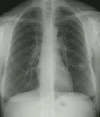

The patient's CXR demonstrates a nodular density in the left lower lung. A prominent vessel can be seen extending from the hilum towards the lesion.